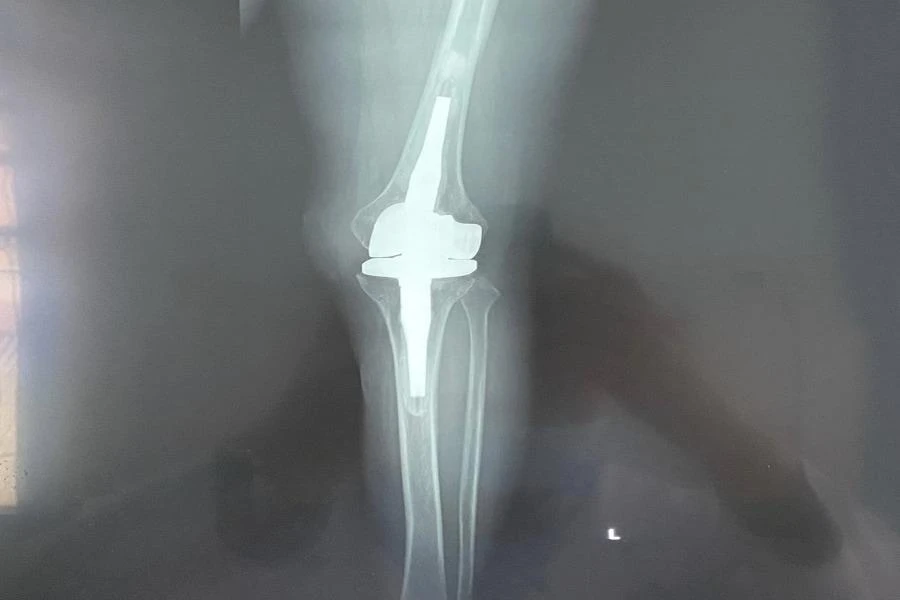

Trước khi phẫu thuật, ê-kip bác sĩ đã sử dụng nhiều hình ảnh chụp chiếu khác nhau nhằm dựng hình toàn bộ khớp gối và gửi cho đối tác tại Đức để chọn một khớp gối bằng titanium vừa vặn kích thước với khớp gối của bệnh nhân.

Khớp gối nhân tạo đặt từ Đức về được thay cho bệnh nhân. Ảnh: BVCC